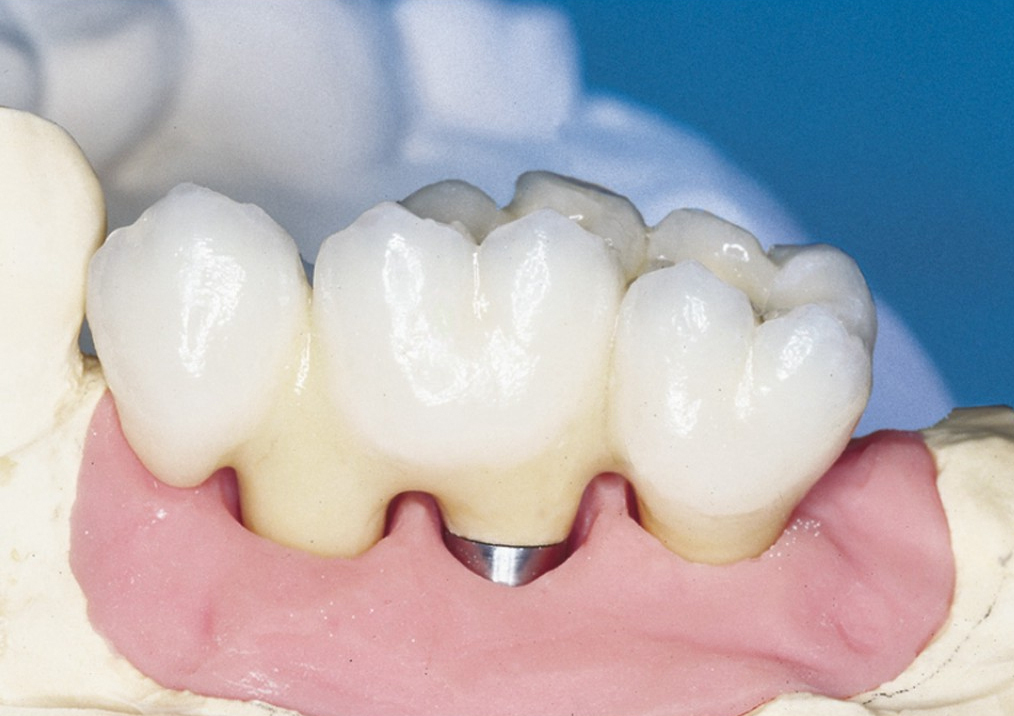

Protetické řešení může být pomocí můstku, který je kotvený na implantátech nebo pomocí jednotlivých korunek na implantátech.

V zásadě je možné do těchto můstků zařadit i přirozené zuby, zejména pokud je potřeba tyto zuby ošetřit proteticky – korunkami. Korunky nebo můstky mohou být na implantáty nacementovány nebo přišroubovány.